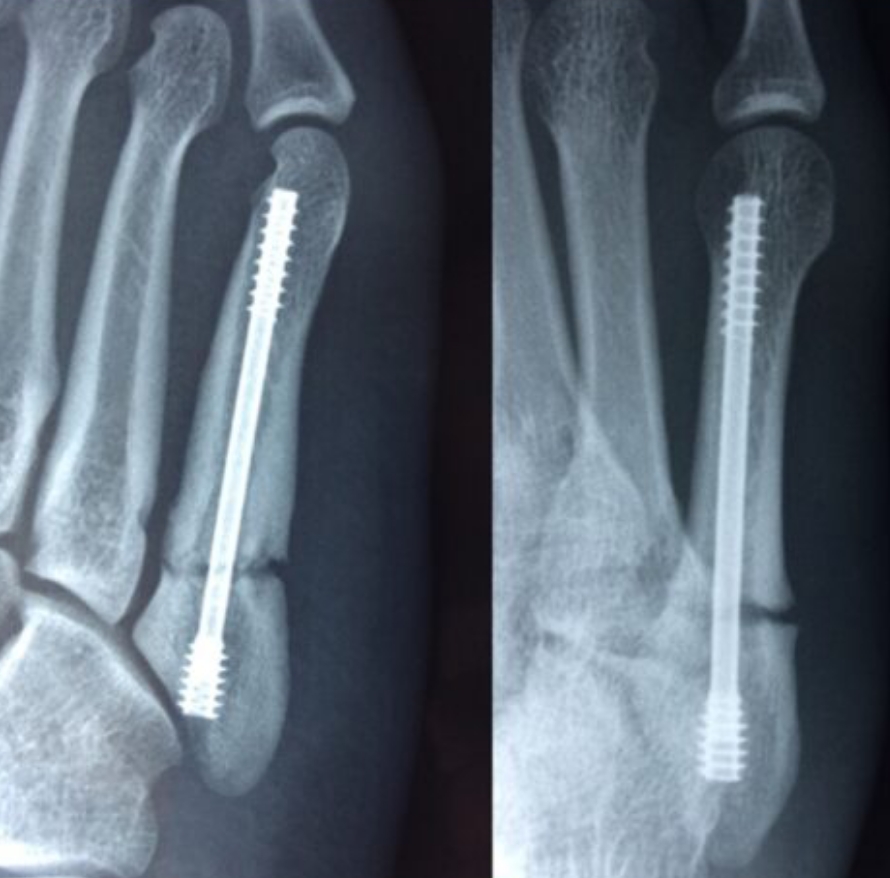

2020-12-09 スポーツ整形 ページ内リンク 第5中足骨骨折(ジョーンズ骨折)【スポーツ整形外科】 第5中足骨骨折(ジョーンズ骨折)【スポーツ整形外科】 サッカーやバスケット等の切り返しの多い競技にしばしば発生する。⇒スクリューによる固定で2〜3か月で復帰。 術前 術後 術後12週間 関連ページ スポーツ整形 一覧へ戻る